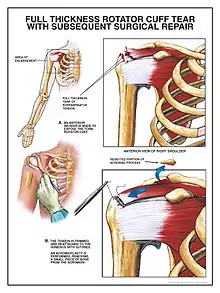

| Some of the muscles of the rotator cuff, with a tear in the supraspinatus muscle | |

Surgery

The three general surgical approaches are arthroscopic, mini open, and open-surgical repair.[29] In the past, small tears were treated arthroscopically, while larger tears would usually require an open procedure. Advances in arthroscopy now allow arthroscopic repair of even the largest tears, and arthroscopic techniques are now required to mobilize many retracted tears. The results match open surgical techniques, while permitting a more thorough evaluation of the shoulder at time of surgery, increasing the diagnostic value of the procedure, as other conditions may simultaneously cause shoulder pain. Arthroscopic surgery also allows for shorter recovery time[29] although differences in postoperative pain or pain medication use are not seen between arthroscopic- and open-surgery.[67] A 2019 review found that the evidence does not support decompression surgery in those with more than 3 months of shoulder pain without a history of trauma.[68]

If a significant bone spur is present, any of the approaches may include an acromioplasty, a subacromial decompression, as part of the procedure.[70] Subacromial decompression, removal of a small portion of the acromion that overlies the rotator cuff, aims to relieve pressure on the rotator cuff in certain conditions and promote healing and recovery.[36] Although subacromial decompression may be beneficial in the management of partial and full-thickness tear repair, it does not repair the tear itself and arthroscopic decompression has more recently been combined with "mini-open" repair of the rotator cuff, allowing for the repair of the cuff without disruption of the deltoid origin.[71] The results of decompression alone tend to degrade with time, but the combination of repair and decompression appears to be more enduring.[72] Subacromial decompression may not improve pain, function, or quality of life.[73]

Repair of a complete, full-thickness tear involves tissue suture. The method currently in favor is to place an anchor in the bone at the natural attachment site, with resuture of torn tendon to the anchor. If tissue quality is poor, mesh (collagen, Artelon, or other degradable material) may be used to reinforce the repair. Repair can be performed through an open incision, again requiring detachment of a portion of the deltoid, while a mini-open technique approaches the tear through a deltoid-splitting approach. The latter may cause less injury to muscle and produce better results.[72] Contemporary techniques now use an all arthroscopic approach. Recovery can take as long as three–six months, with a sling being worn for the first one–six weeks.[74] In the case of partial thickness tears, if surgery is undertaken, tear completion (converting the partial tear to a full tear) and then repair, is associated with better early outcomes than transtendinous repairs (where the intact fibres are preserved) and no difference in failure rates.[75]